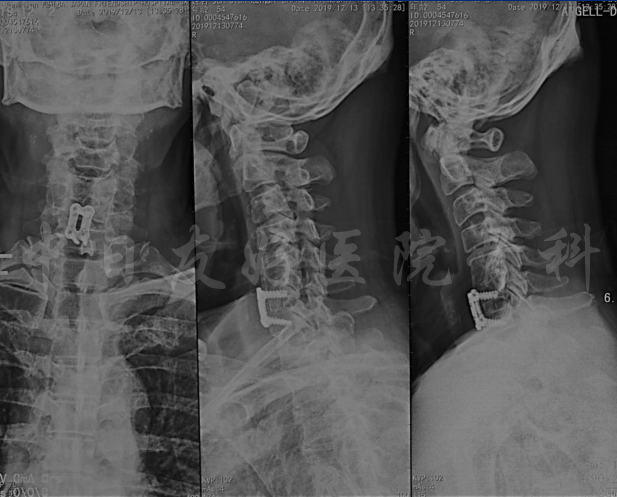

颈椎X片

颈椎MRI

颈椎MRI

颈椎各节段MRI(上下滑动)

颈CT(上下滑动)

术后影像片